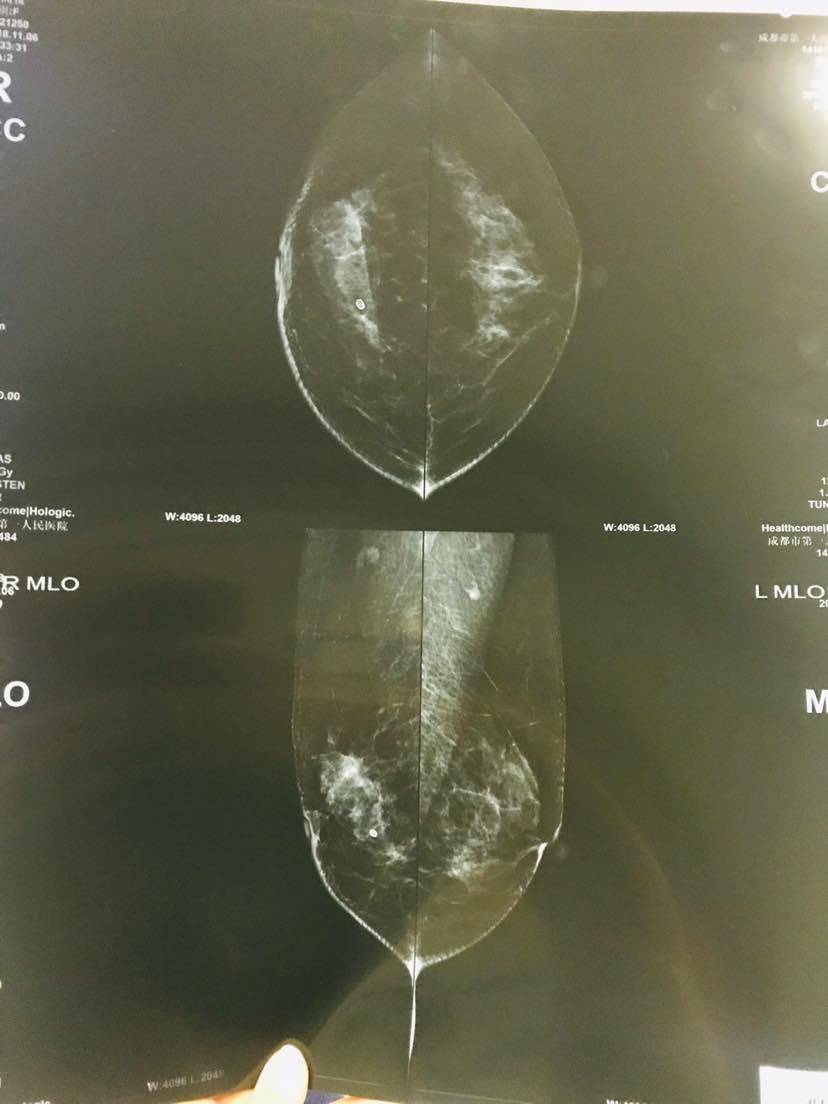

这是第一家医院做的检查

第二家的。有懂的朋友吗?我们也做了最坏的打算,会和我妈妈一起努力的!